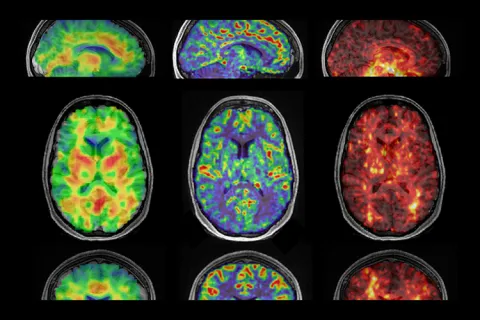

Linking blood flow and brain health

ME researchers, led by Associate Professor Mehmet Kurt, are using imaging methods to learn how blood flow may impact the hippocampus.